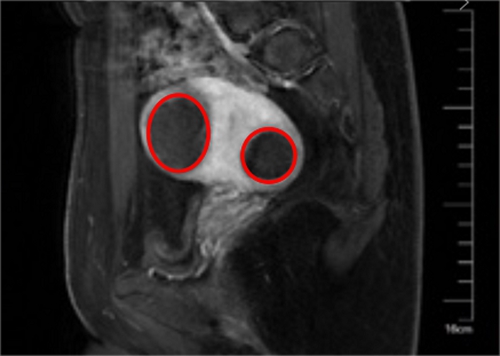

▲ 術(shù)后

入院后,醫(yī)院微無(wú)創(chuàng)中心團(tuán)隊(duì)成功利用聚焦超聲消融術(shù)為張女士消除肌瘤,術(shù)后4個(gè)小時(shí),張女士就已經(jīng)在病房里端起筆記本開(kāi)始工作了。術(shù)后第二天,張女士順利出院,并一再向醫(yī)護(hù)人員表示感謝:“沒(méi)想到竟然還有這種治療方式,不僅手術(shù)沒(méi)有創(chuàng)口,還可以提前計(jì)劃我的媽媽夢(mèng),真是太好了!”